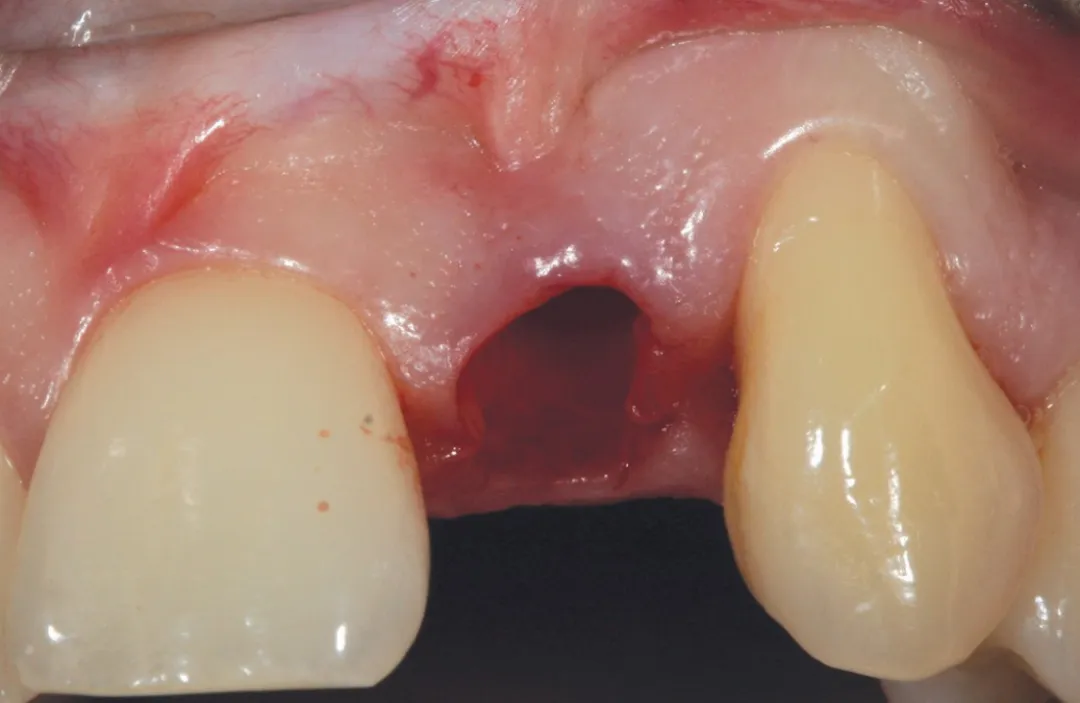

2 号病例 - Patrick EXBRAYAT 医生(图 21 至 35)

22 岁患者,23 异位,行正颌外科种植术后 22 出现严重根吸收。

图 21 :术前临床检查。

图 23 :拔牙后手术区域。

图 24 :植入 Axiom® 2.8 x 14 种植体。